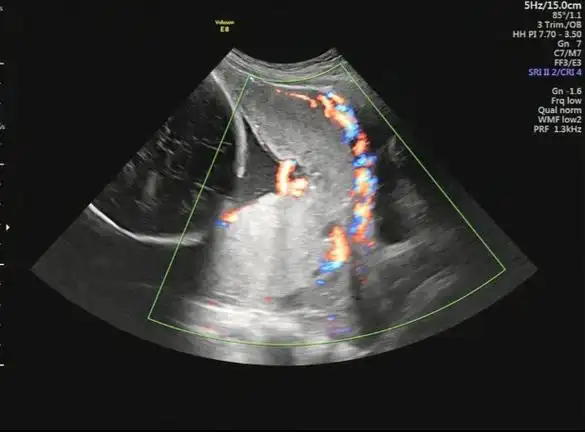

胎盘植入

潍坊市人民医院一例凶险性前置胎盘合并胎盘植入产妇顺利分娩

关于胎盘植入性疾病mri检查的联合共识要点解读

惊险生娃碰到胎盘植入龙川妇幼多学科协作助产妇渡劫成功